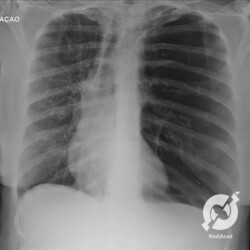

Este é o típico caso de pneumotórax. Um cara compridão, longilíneo, com dor torácica e dispneia súbitas. Na radiografia a gente percebe que não tem marcas de parênquima no ápice esquerdo e que existe uma linha de pleura lateralmente. Pneumotórax espontâneo